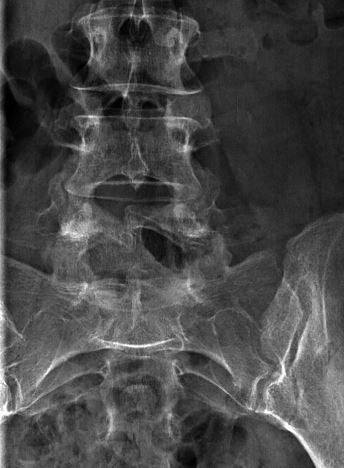

2) Инфантильная гемангиома ( рис 6С ) является сосудистым, как правило, приподнятым над уровнем кожи поражением, имеющим четко определенные границы. Ее легко отличить от плоских портвейновых, розовых или лососевых пятен, которые являются капиллярными пороками развития, и также описаны ниже, в разделе «Кожные аномалии среднего риска». Инфантильные гемангиомы развиваются у 5% младенцев и могут находиться в любом месте тела. Только инфантильные гемангиомы, которые располагаются на срединной линии тела над позвоночником, особенно в поясничной области, бывают связаны с лежащими под ними дистракными пороками развития.